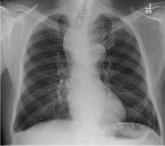

A 60-year-old man presents for evaluation of fever, cough, and back pain. His symptoms have been intermittent but have worsened over the past month or...